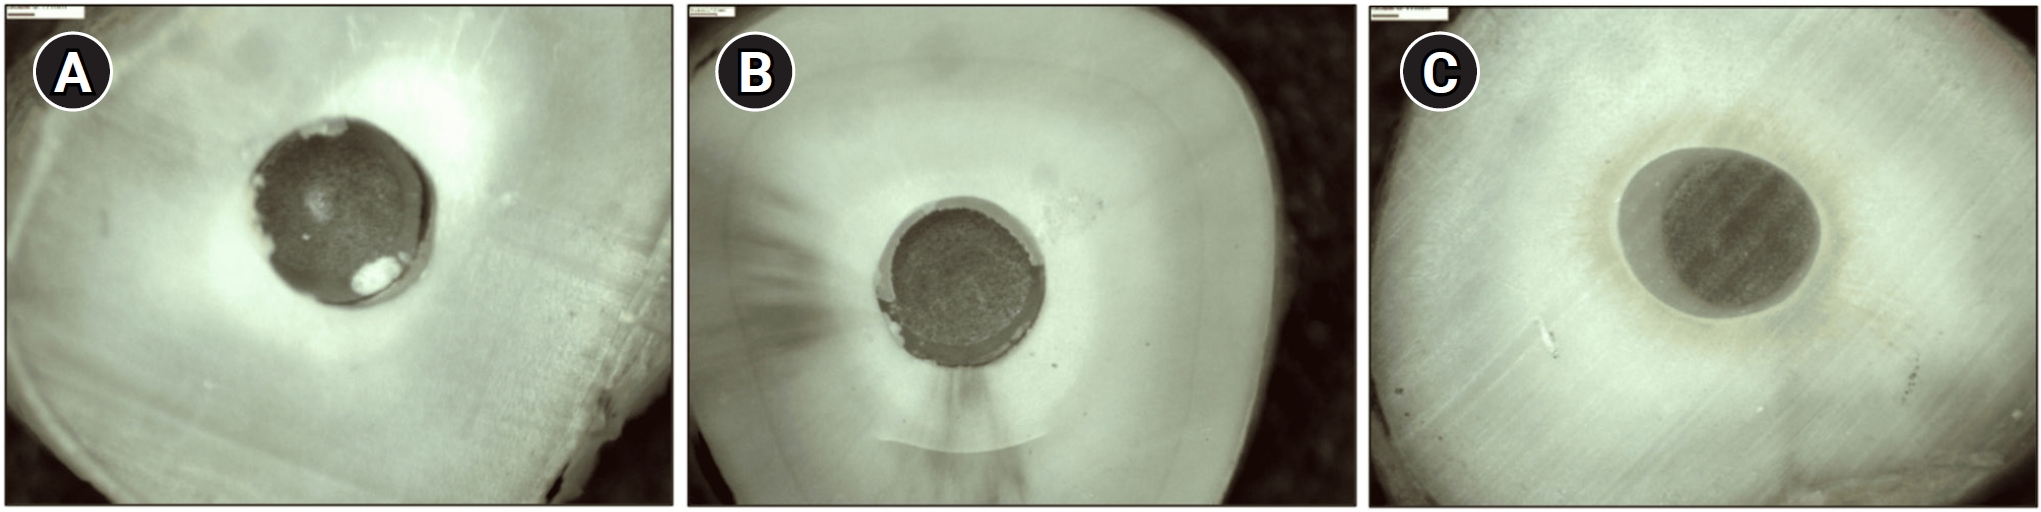

Forty central human incisors were randomly divided into four groups (n = 10) based on sealer (epoxy resin-based or calcium silicate-based) and cement (conventional and self-adhesive resin) types: AH Plus (Dentsply DeTrey)/RelyX ARC (3M ESPE), AH Plus/RelyX U200 (3M ESPE), Bio-C Sealer (Angelus)/RelyX ARC, and Bio-C Sealer/RelyX U200. After canal filling and post cementation, roots were sectioned to obtain one specimen per root third. A push-out test and failure pattern assessment were conducted, with bond strength analyzed using the one-way analysis of variance and Tukey test.

AH Plus/RelyX ARC showed the highest bond strength values, with a significant difference in the middle third. The most common failure was mixed (55%), while adhesive failures made up 45%, with 23.5% at the cement/post interface and 21.5% at the cement/dentin interface.